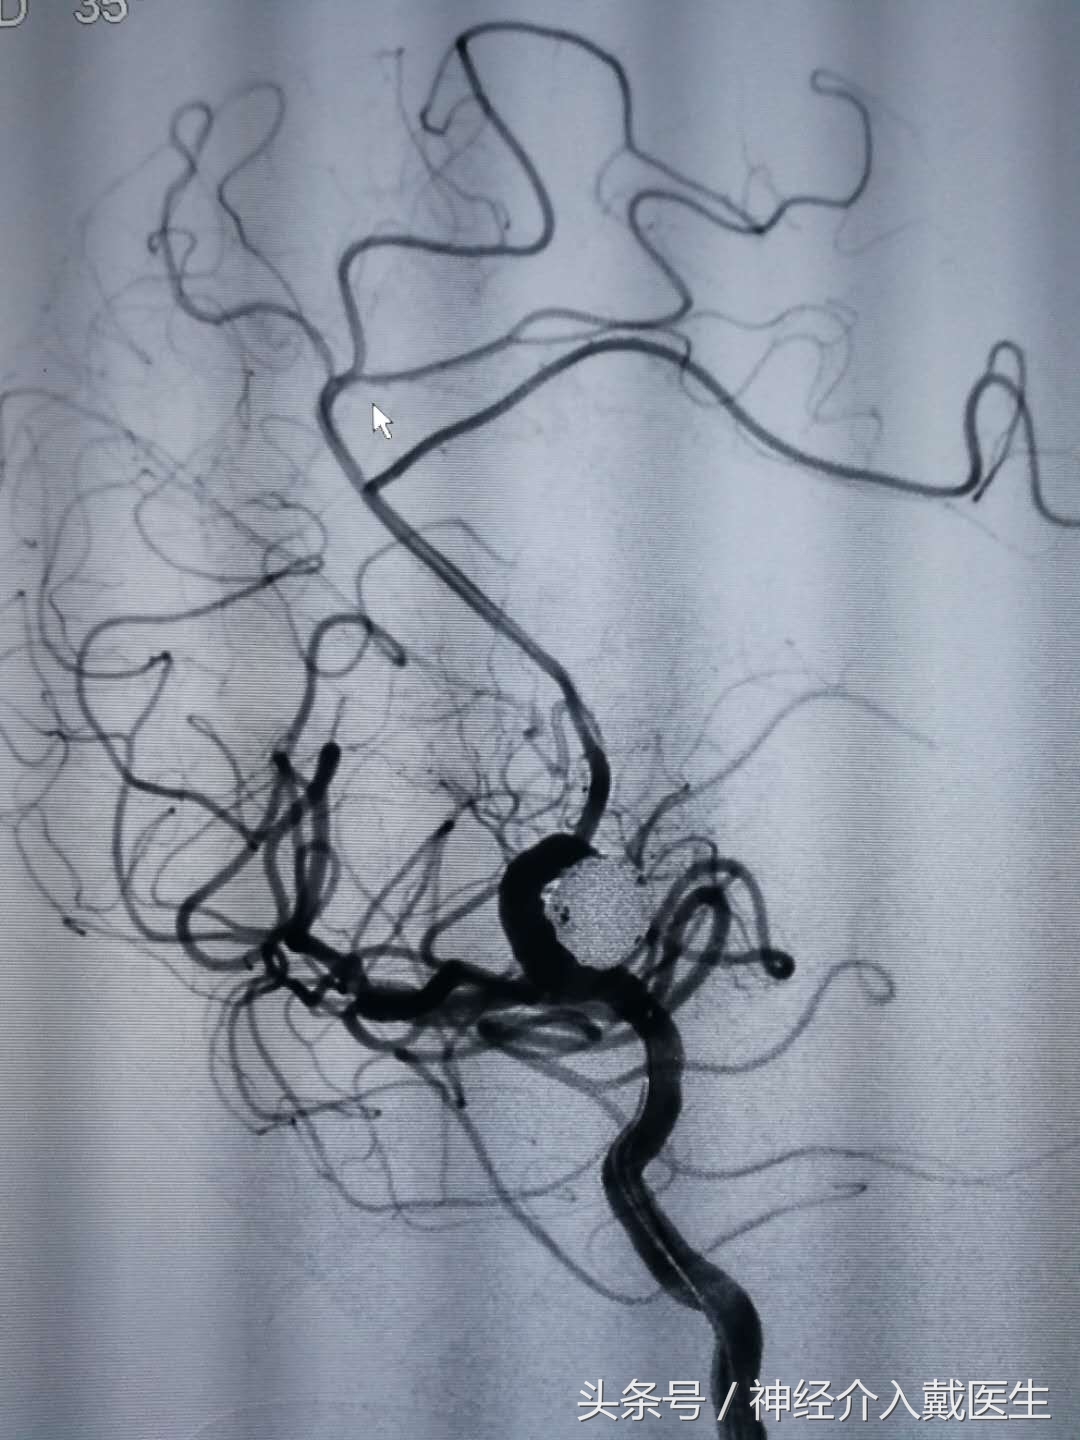

工作位显示载瘤动脉通畅,瘤颈填塞满意

本例病人,用稍大的相当于18系弹簧圈成篮,有利于填塞瘤颈,因为粗的弹簧圈张力较高,虽然不利于术者的操作,但是有利于弹簧圈稳定在动脉瘤内,即使裸栓也不易逃逸到载瘤动脉,有效的减少并发症的发生。

在填塞过程中使用较多的国产弹簧圈,大大的降低了治疗费用,降低了病人的经济负担,操作过程中,国产弹簧圈与进口弹簧圈的手感并无明显不同,只有弹簧圈的解脱稍微复杂一点点,也是比较简单的。